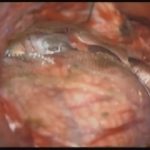

摘出 中

摘出 後